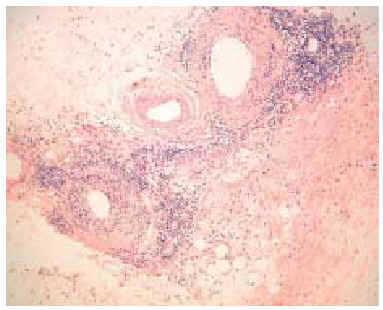

En septiembre de 1999 presentó un nuevo brote de lesiones cutáneas clásicas de dermatomiositis, así como 5 lesiones nodulares en ambos miembros superiores, de unos 3 cm de diámetro, dolorosas, induradas, de superficie poiquilodérmica, sin sintomatología muscular ni elevación de las enzimas musculares. Se realizó una biopsia cutánea de un nódulo del brazo que puso de manifiesto una degeneración vacuolar focal de la capa basal epidérmica y un leve infiltrado inflamatorio linfohistiocitario perivascular en la dermis. Lo más llamativo fue la presencia de una paniculitis de predominio lobulillar con linfocitos, histiocitos y células plasmáticas (fig. 2). En algunas zonas los linfocitos formaban acumulaciones donde se insinuaba un centro germinal (fig. 3) y en otras infiltraban la pared de los vasos (fig. 4).

Fig. 2.--Paniculitis lobulillar con linfocitos y células plasmáticas. (Hematoxilina-eosina, x40.)